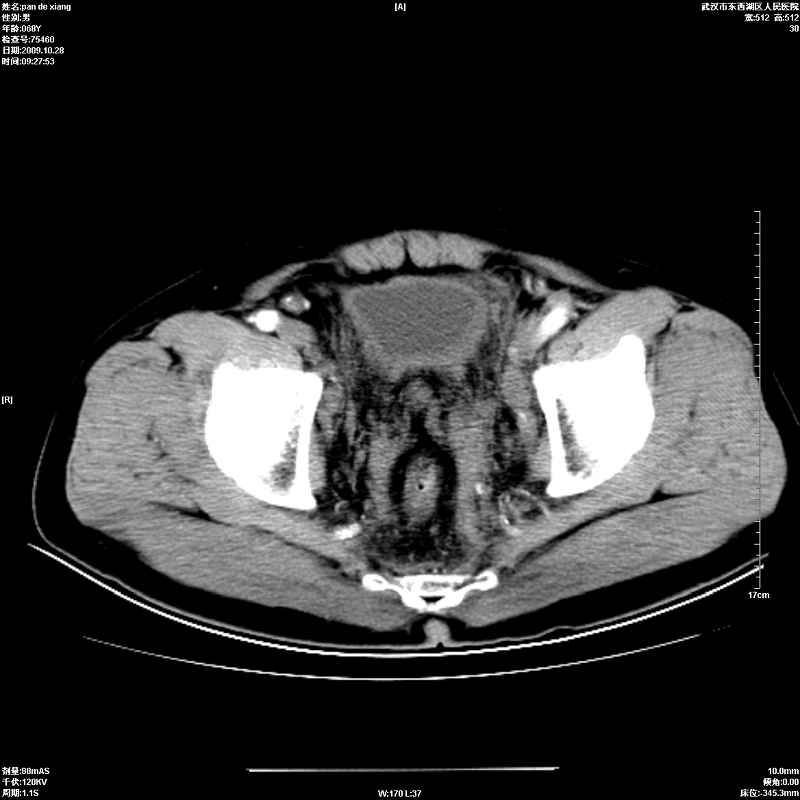

以下是引用杀毒软件在2009-10-28 20:41:00的发言:[br]结合临床考虑---白血病双肾改变或淋巴瘤。

以下是引用zxl51642在2009-10-29 9:59:00的发言:[br]结合临床“单克隆免疫球蛋白血症”,考虑双肾为继发损害并肾功能不全(尿中大量igg及少量iga、igm等大分子免疫球蛋白滤出所致继发损害),椎前软组织肿块为髓外造血。与浆细胞瘤有区别,平扫时有战友说的很清楚。